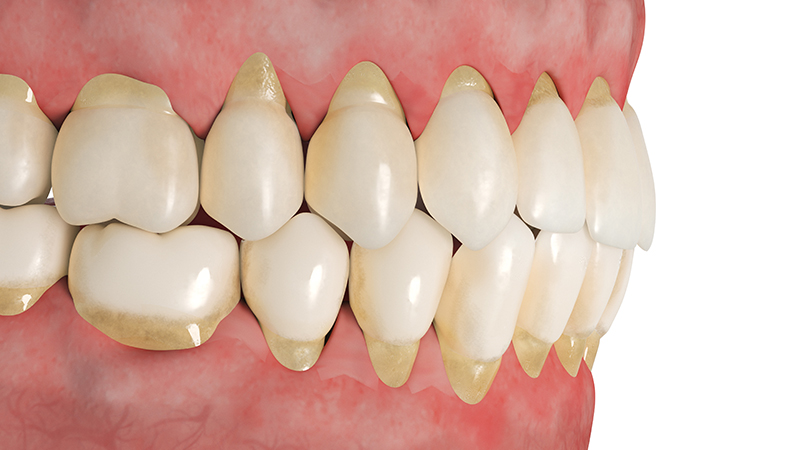

내려앉는 잇몸

잇몸질환이 시작되면 잇몸이 치아를 제대로 감싸지 못해 잇몸과 치아가 내려앉습니다.